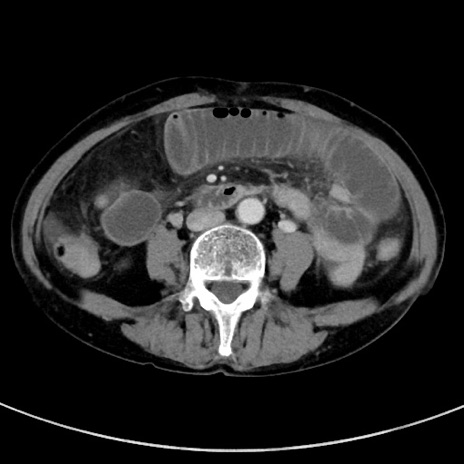

症例23(横断像)

【症例】70歳代女性

【主訴】下腹部痛・嘔吐

【現病歴】2日前より腹痛あり。昨日嘔吐あり。症状改善しないため来院。

【既往歴】胃GISTに対して胃部分切除後。

【身体所見】BT 37.1℃、BP 128/77mmHg、腹部:平坦・軟、下腹部に圧痛あり。

【データ】WBC 10200、CRP 0.31